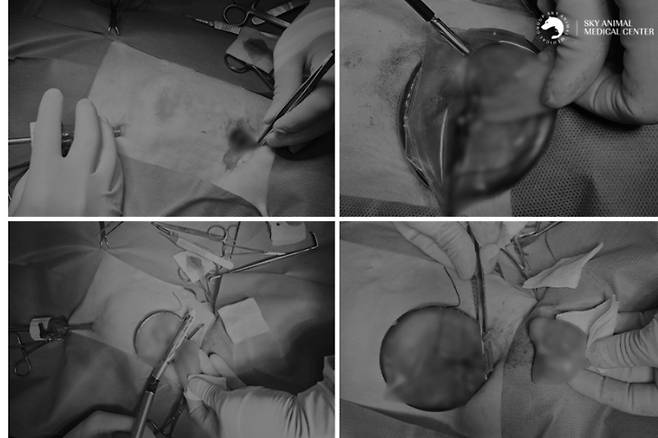

수술은 개흉 범위를 최소화하고 통증·감염·조직 손상 위험을 줄이기 위해 흉강경을 이용한 최소 침습 방식으로 진행됐다. 흉강경 수술은 흉부(가슴 안쪽)의 질환을 수술할 때 갈비뼈 사이에 작은 구멍을 뚫고 특수 내시경을 삽입해 진행하는 방식이다.

수술을 맡은 문종선 인천 스카이동물메디컬센터 대표원장은 병변이 위치한 폐엽만 정밀하게 절제해 주변 조직의 손상을 최소화했다.

수술 후 바람이는 큰 문제 없이 마취에서 회복했다. 흉강경 수술 덕분에 일반 개흉 수술보다 회복 속도가 빠르고 통증도 훨씬 적었다.